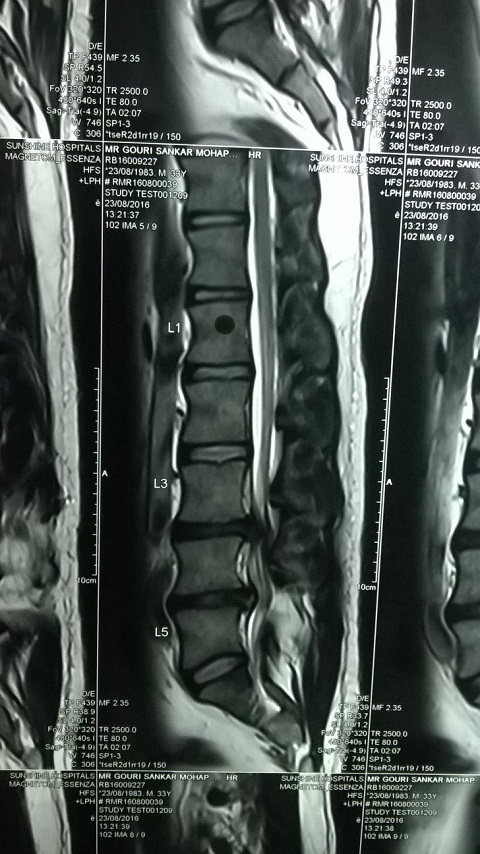

MRI of Gouri Shankar Mohapatra